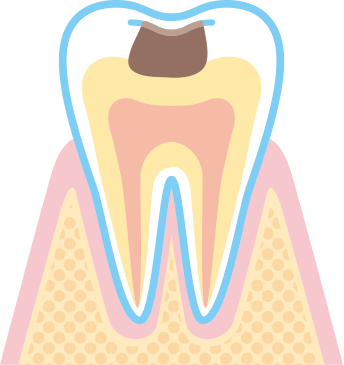

エナメル質から象牙質に達し状態です。

痛みはあまりありませんが冷たいものがしみ始めます。

インレー(患部を削ったあとの被せ物)やクラウン(患部を削ったあとの冠状被せ物) などの詰め物、被せ物の治療が必要です。